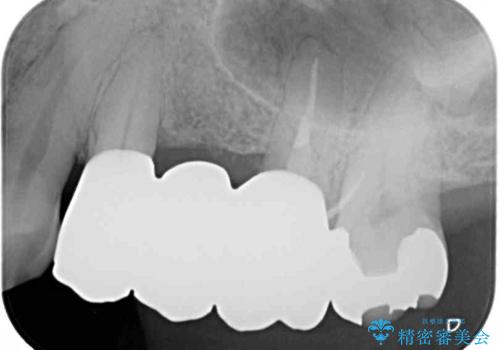

- 奥歯のブリッジにものが挟まるとのことで来院された患者様です。

奥歯の3本の歯根のうち1本は保存困難な状況であったため、1本を抜根し、傷の治癒を待った後にオールセラミックブリッジにて補綴することとしました。

ものが挟まる原因は、保存困難なほど歯肉から露出していた歯根にあったため、抜根することで気になっていた問題は解消されました。